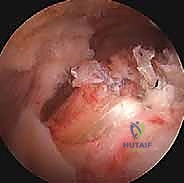

في هذا الدليل الطبي المرجعي والشامل، سنتعمق بشكل غير مسبوق في فهم اعتلال والتهاب وتر العضلة ذات الرأسين. سنبدأ بتشريحه المعقد الذي يجعله عرضة للإصابة، مروراً بالمسببات البيوميكانيكية، وعوامل الخطر، والأعراض السريرية المميزة. وصولاً إلى استعراض شامل لأحدث خيارات التشخيص والعلاج المتاحة عالمياً. وسنركز بشكل مكثف على تقنيات "العلاج بالمنظار الجراحي"، والذي يمثل الثورة الأهم في جراحة الكتف الحديثة، موفراً حلولاً جذرية وفعالة بحد أدنى من التدخل الجراحي.

بصفتنا خبراء رواد في جراحة العظام، المفاصل، والطب الرياضي، فإننا نؤمن إيماناً راسخاً بأهمية التثقيف الطبي وتزويد المرضى بالمعلومات الدقيقة، الموثوقة، والشاملة لتمكينهم من اتخاذ قرارات مستنيرة وواثقة بشأن صحتهم. وفي هذا السياق الطبي المتقدم، يبرز اسم الأستاذ الدكتور محمد هطيف في العاصمة صنعاء كمرجع علمي وطبي رائد في تشخيص وعلاج حالات الكتف الأكثر تعقيداً. بخبرة تتجاوز العشرين عاماً، ومكانة أكاديمية رفيعة كأستاذ في جامعة صنعاء، يسخر الدكتور هطيف أحدث التقنيات الجراحية بالمنظار لضمان استعادة المرضى لوظائفهم الحركية بأعلى درجات الأمان والنجاح.